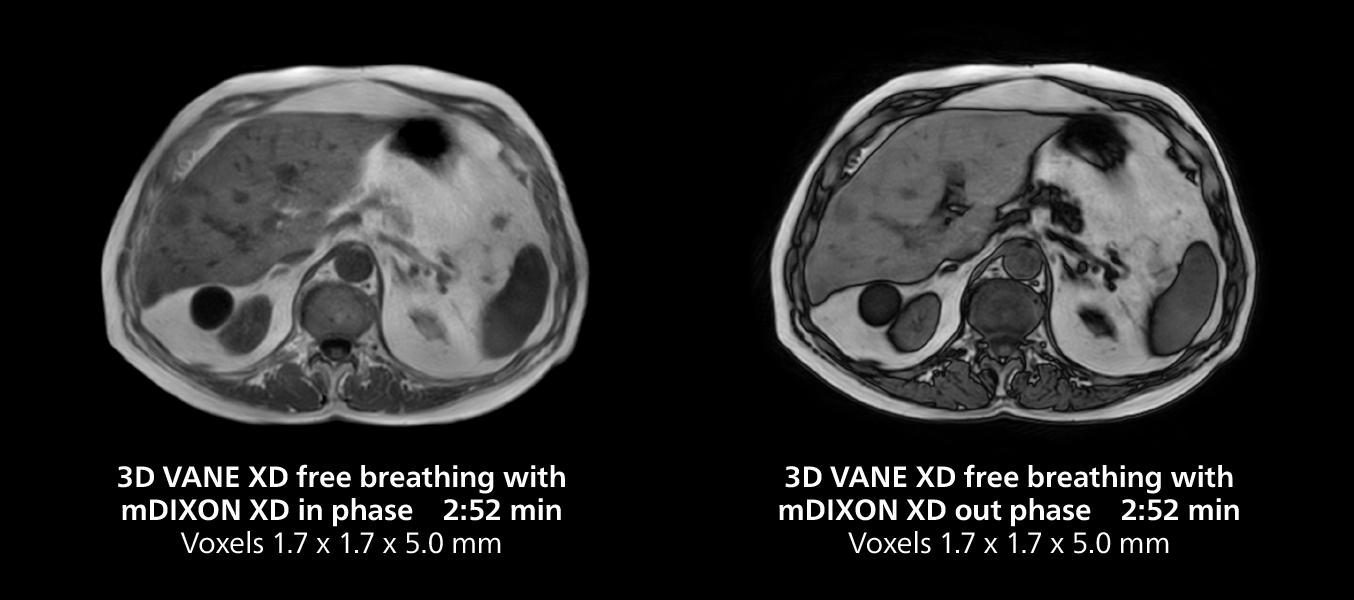

She also uses free breathing with 3D mDIXON to obtain in-phase, water and fat images in a single scan. “It is very reproducible before and after gadolinium, which makes it useful for liver imaging,” she adds.

Liver imaging using MR 5300

This case includes 3D free breathing and 4D dynamic free breathing MRI of a metastasized liver. A high quality fatsat sequence with good resolution is obtained in 1:36 minutes with T2-weighted MultiVane XD.

Liver imaging using MR 5300

This case includes 3D free breathing and 4D dynamic free breathing MRI of a metastasized liver. A high quality fatsat sequence with good resolution is obtained in 1:36 minutes with T2-weighted MultiVane XD.